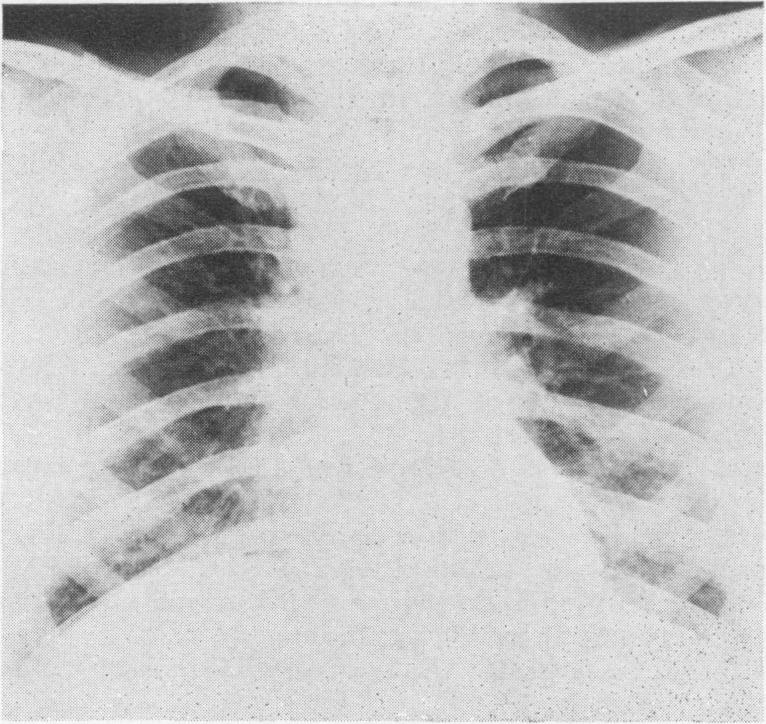

Mediastinoscopy: a diagnostic procedure in hilar and paratracheal lymphadenopathy.

Postgrad Med J. 1971 Nov;47(553):698-704. doi: 10.1136/pgmj.47.553.698.

Mediastinoscopy, in the skilled hands of a thoracic surgeon, is a safe, cosmetically accepted procedure with negligible complications, less than that reported in many series of scalene node biopsies. It has the advantage of yielding a much higher rate of diagnostic tissue, in all instances over 90%. In the cases of tuberculosis it enabled an organism to be isolated and sensitivities obtained. It has also revealed a group of cases with findings, a further study of which may increase our understanding, assessment and management of patients presenting with hilar and/or paratracheal lymphadenopathy.